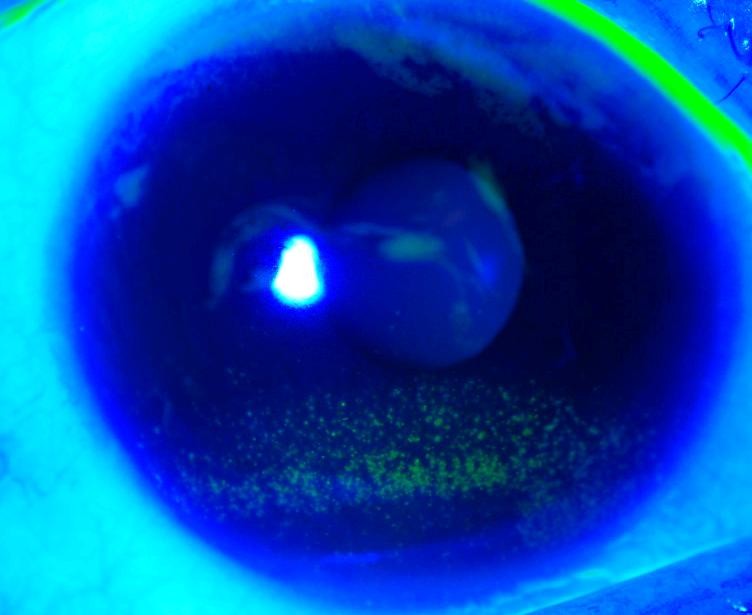

Nhuộm thuốc fuorescein lên giác mạc giữa mi mắt ở bệnh nhân bị khô mắt